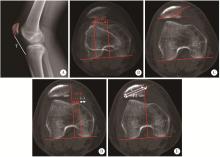

Figure 2

Examples of 4-grade Dejour classification based on axial CT A, a 38-year-old male was diagnosed with Dejour A trochlear dysplasia, whose CT scan indicated a trochlear groove angle of >145 degree and symmetric trochlear facets; B, a 21-year-old male was diagnosed with Dejour B trochlear dysplasia, whose CT scan indicated a flat trochlea (arrow); C, a 16-year-old female was diagnosed with Dejour C trochlear dysplasia, whose CT scan indicated asymmetric trochlear facets and hypoplastic medial facet (arrow); D, a 17-year-old female was diagnosed with Dejour D trochlear dysplasia, whose CT scan indicated a positive cliff pattern (arrow). CT, computed tomography."